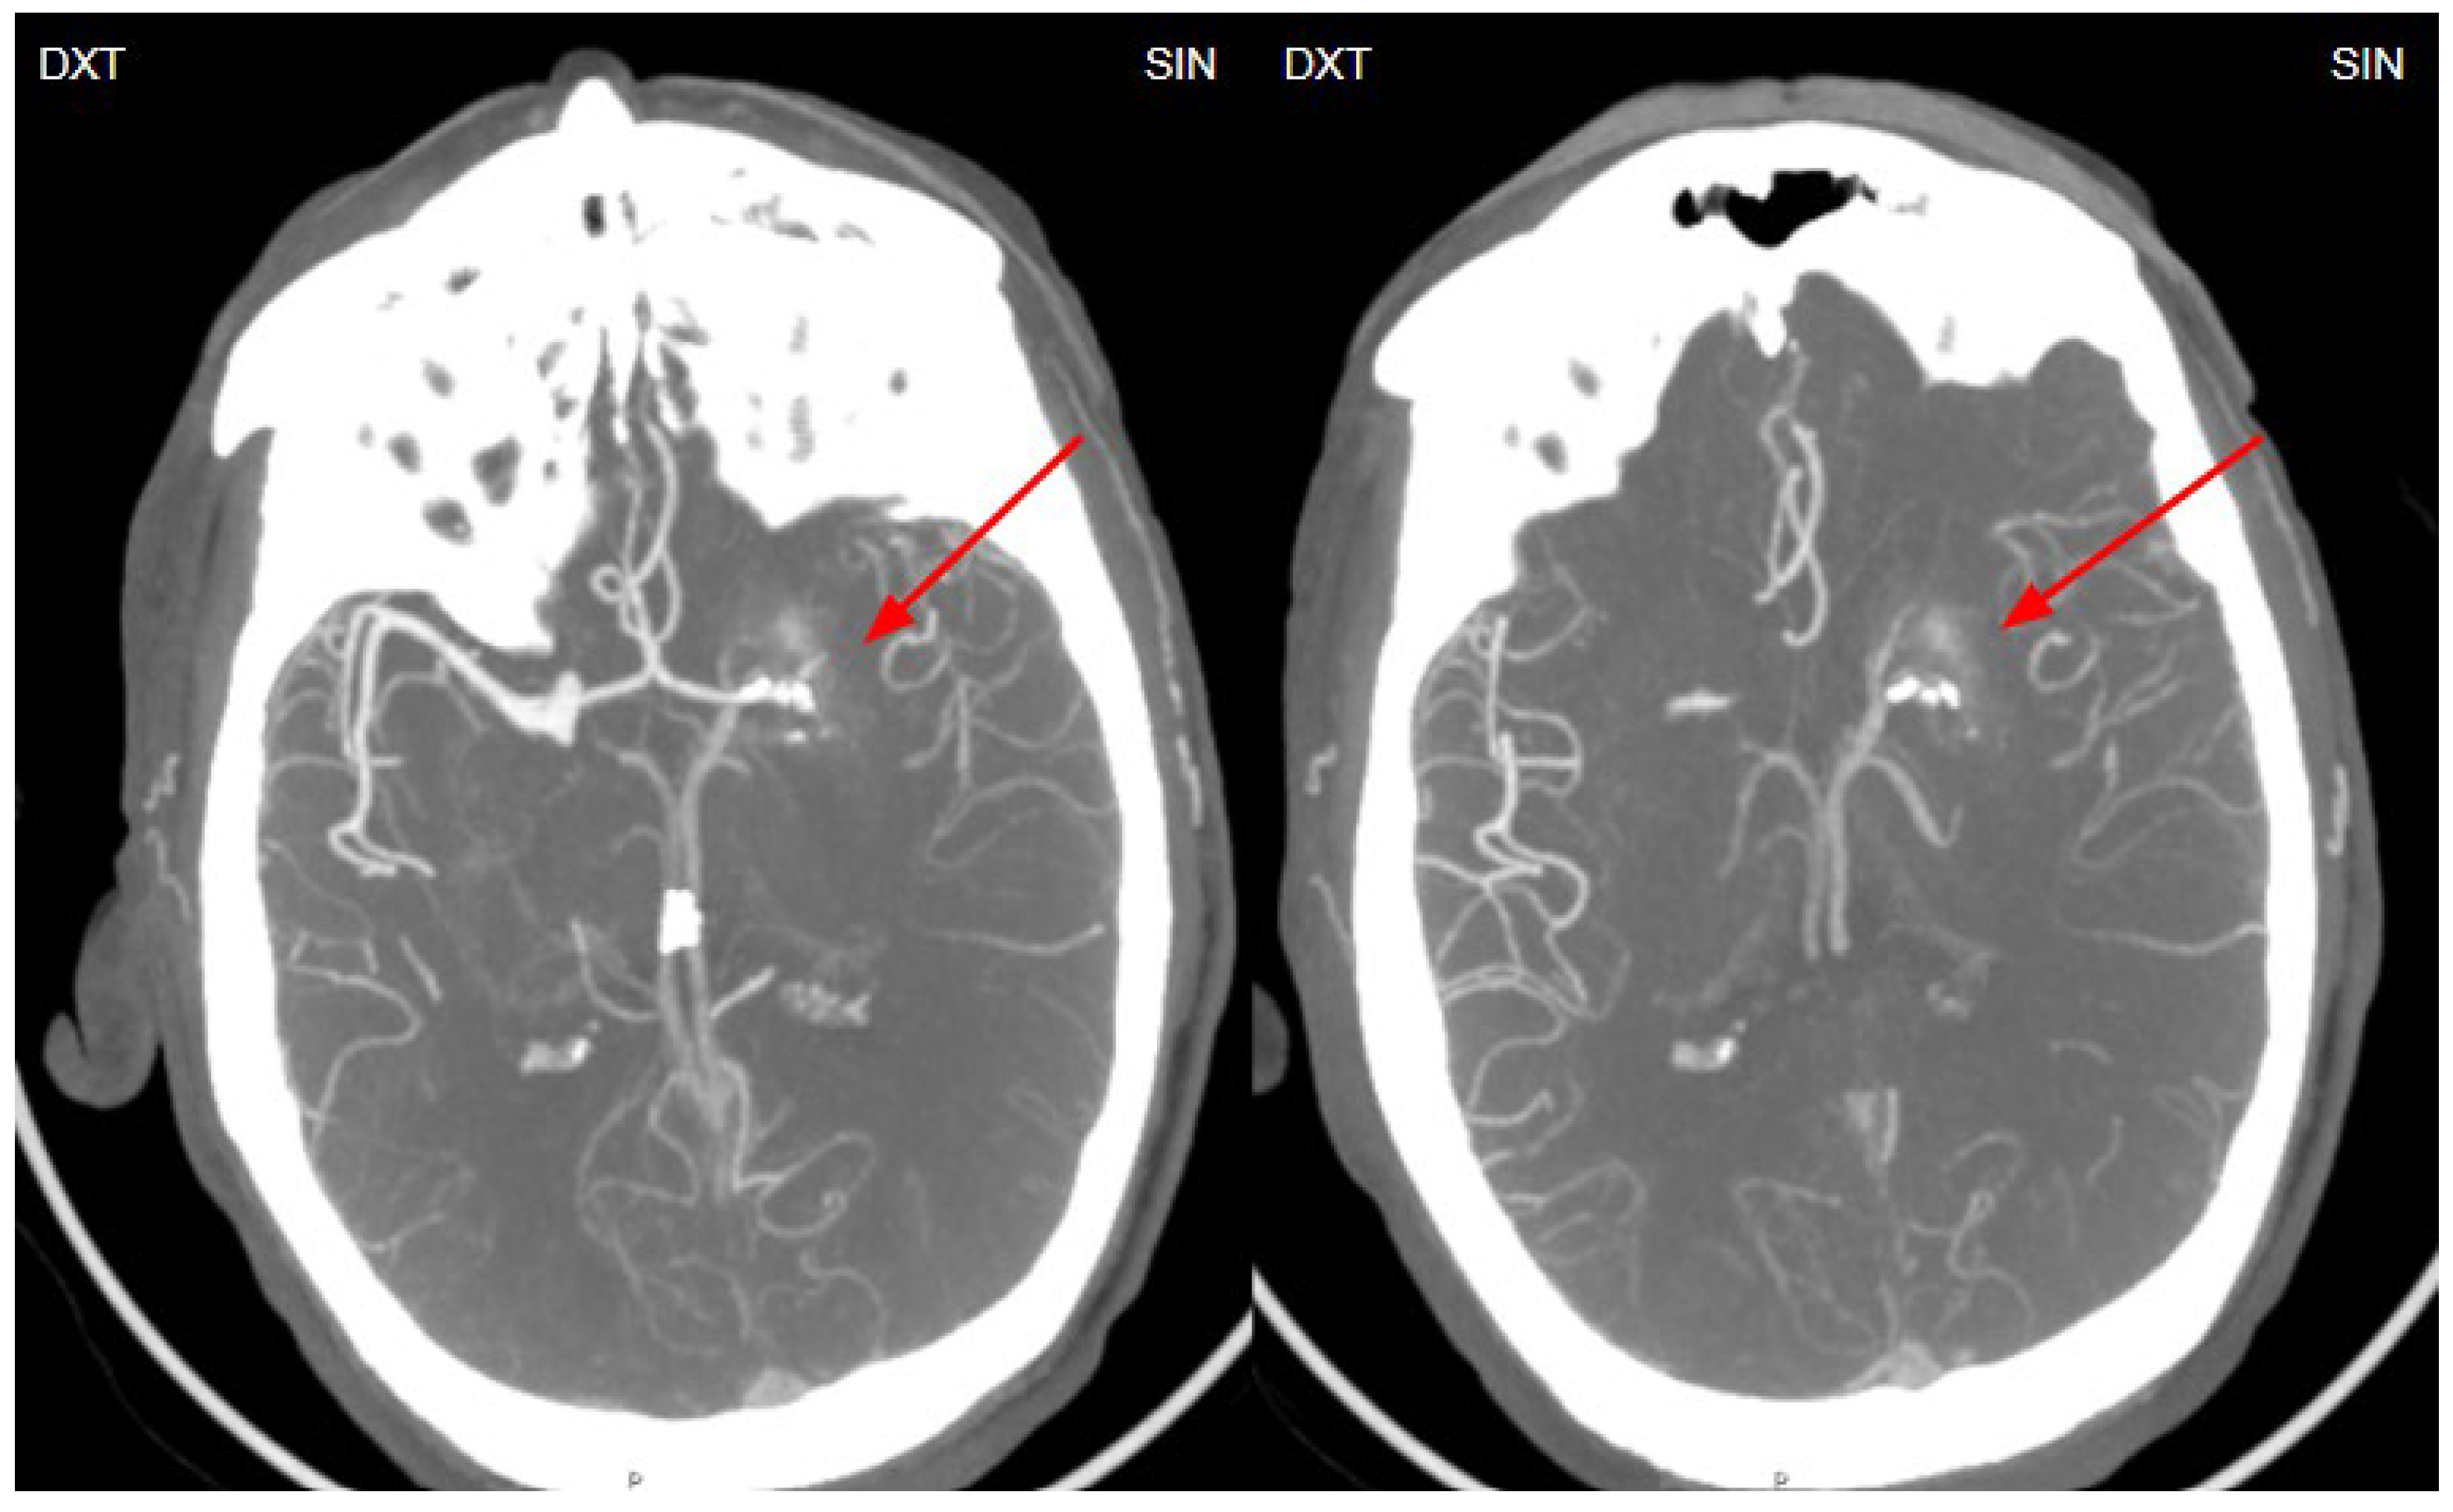

Figure 4. Retrospective analysis of the computed tomography angiography (MIP-CTA) images, performed before the MRI and DSA examinations, reveals a small venous angioma (DVA) in the left basal ganglia (red arrows).

In 2010, Dehkharghani et al. published an article demonstrating six case reports with unilateral caudate and putamen calcifications in DVA drainage territories. In all these patients, DVA was found in gadolinium-enhanced MRI and/or computed tomography angiography (CTA) or conventional angiography. They stressed out the venous hypertension as the main contributing factor for these abnormalities [22]. Moreover, they reported no symptoms referable to the basal ganglia, and patients they presented did not reveal underlying metabolic disorders or processes associated with calcium deposition [22]. In our case, the patient was a fifty-four-year-old male presenting with a sudden speech impairment and right-sided weakness. No abnormal movements were noted in this patient. Subacute stroke on the left side in the dorsal part of the insula, in the upper dorsal part of the left temporal lobe and partially in the left parietal lobe was found on NECT, and CTA revealed left middle cerebral artery (MCA) M2 occlusion. On CT perfusion (CTP), markedly decreased cerebral blood flow (CBF) and cerebral blood volume (CBV) was noted along with increased mean transit time (MTT). Subsequently, gadolinium-enhanced brain MRI was performed where small blood vessels draining to subependymal periventricular veins on T1 post-contrast was found. Due to these findings, the patient underwent following digital subtraction angiography (DSA) where venous angioma in the area of ​​the left basal ganglia was observed.